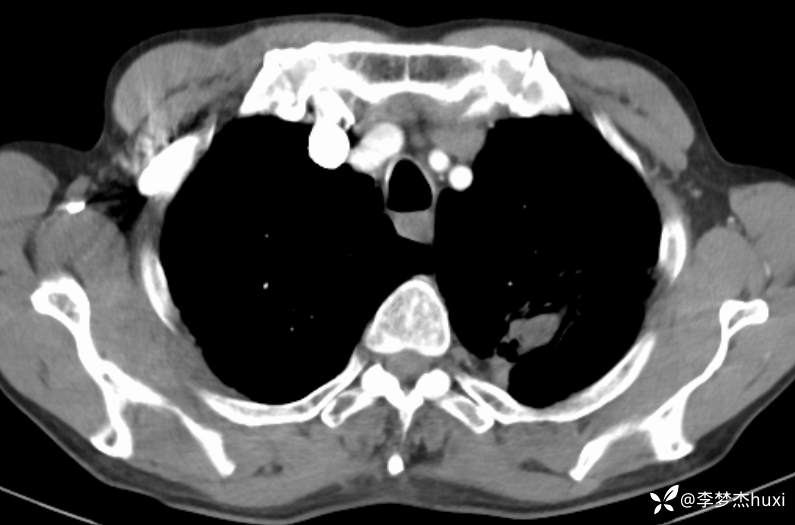

1.现病史:患者老年 男,患者于入院前7天“感冒”后出现咳嗽、咳痰,为白痰,不易咳出,伴胸闷憋气,活动后加重,病初发热,最高达38.0℃,无胸痛,无咯血,无腹痛、腹泻,无恶心、呕吐,无尿频、尿急、尿痛,院外给予口服药物(自诉口服药物,具体药物名称不详)治疗,病情无明显好转,6-13于我院门诊查胸部CT:左肺上叶软组织密度影-性质待定,双肺炎症,双肺气肿,双肺大泡,双肺部分实性结节-炎症?双肺实性结节,主动脉及冠状动脉钙化,双侧胸膜局限性增厚;肝脏多发囊性病变。6-14查胸部增强CT:左肺上叶空洞-真菌感染?占位不除外;双肺炎症,双肺气肿,双肺大泡,双肺部分实性结节-考虑炎症,双肺实性结节,主动脉及冠状动脉钙化,双侧胸膜局限性增厚;肝脏多发囊性病变;今日为进一步诊治来我院;门诊以“肺空洞”收入院。